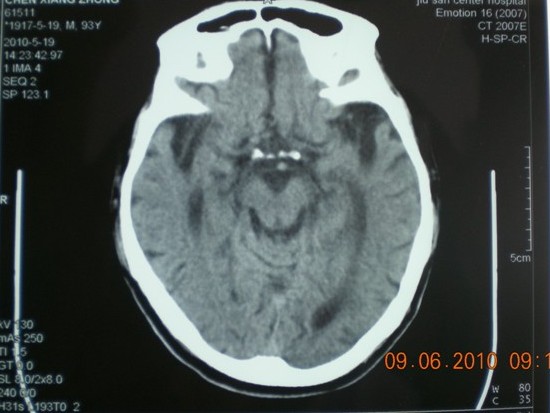

标题: CT27297:头晕 双下肢无力两天 [打印本页]

标题: CT27297:头晕 双下肢无力两天

图片太小,感觉有脑萎缩。

脑萎缩

脑萎缩。

85岁